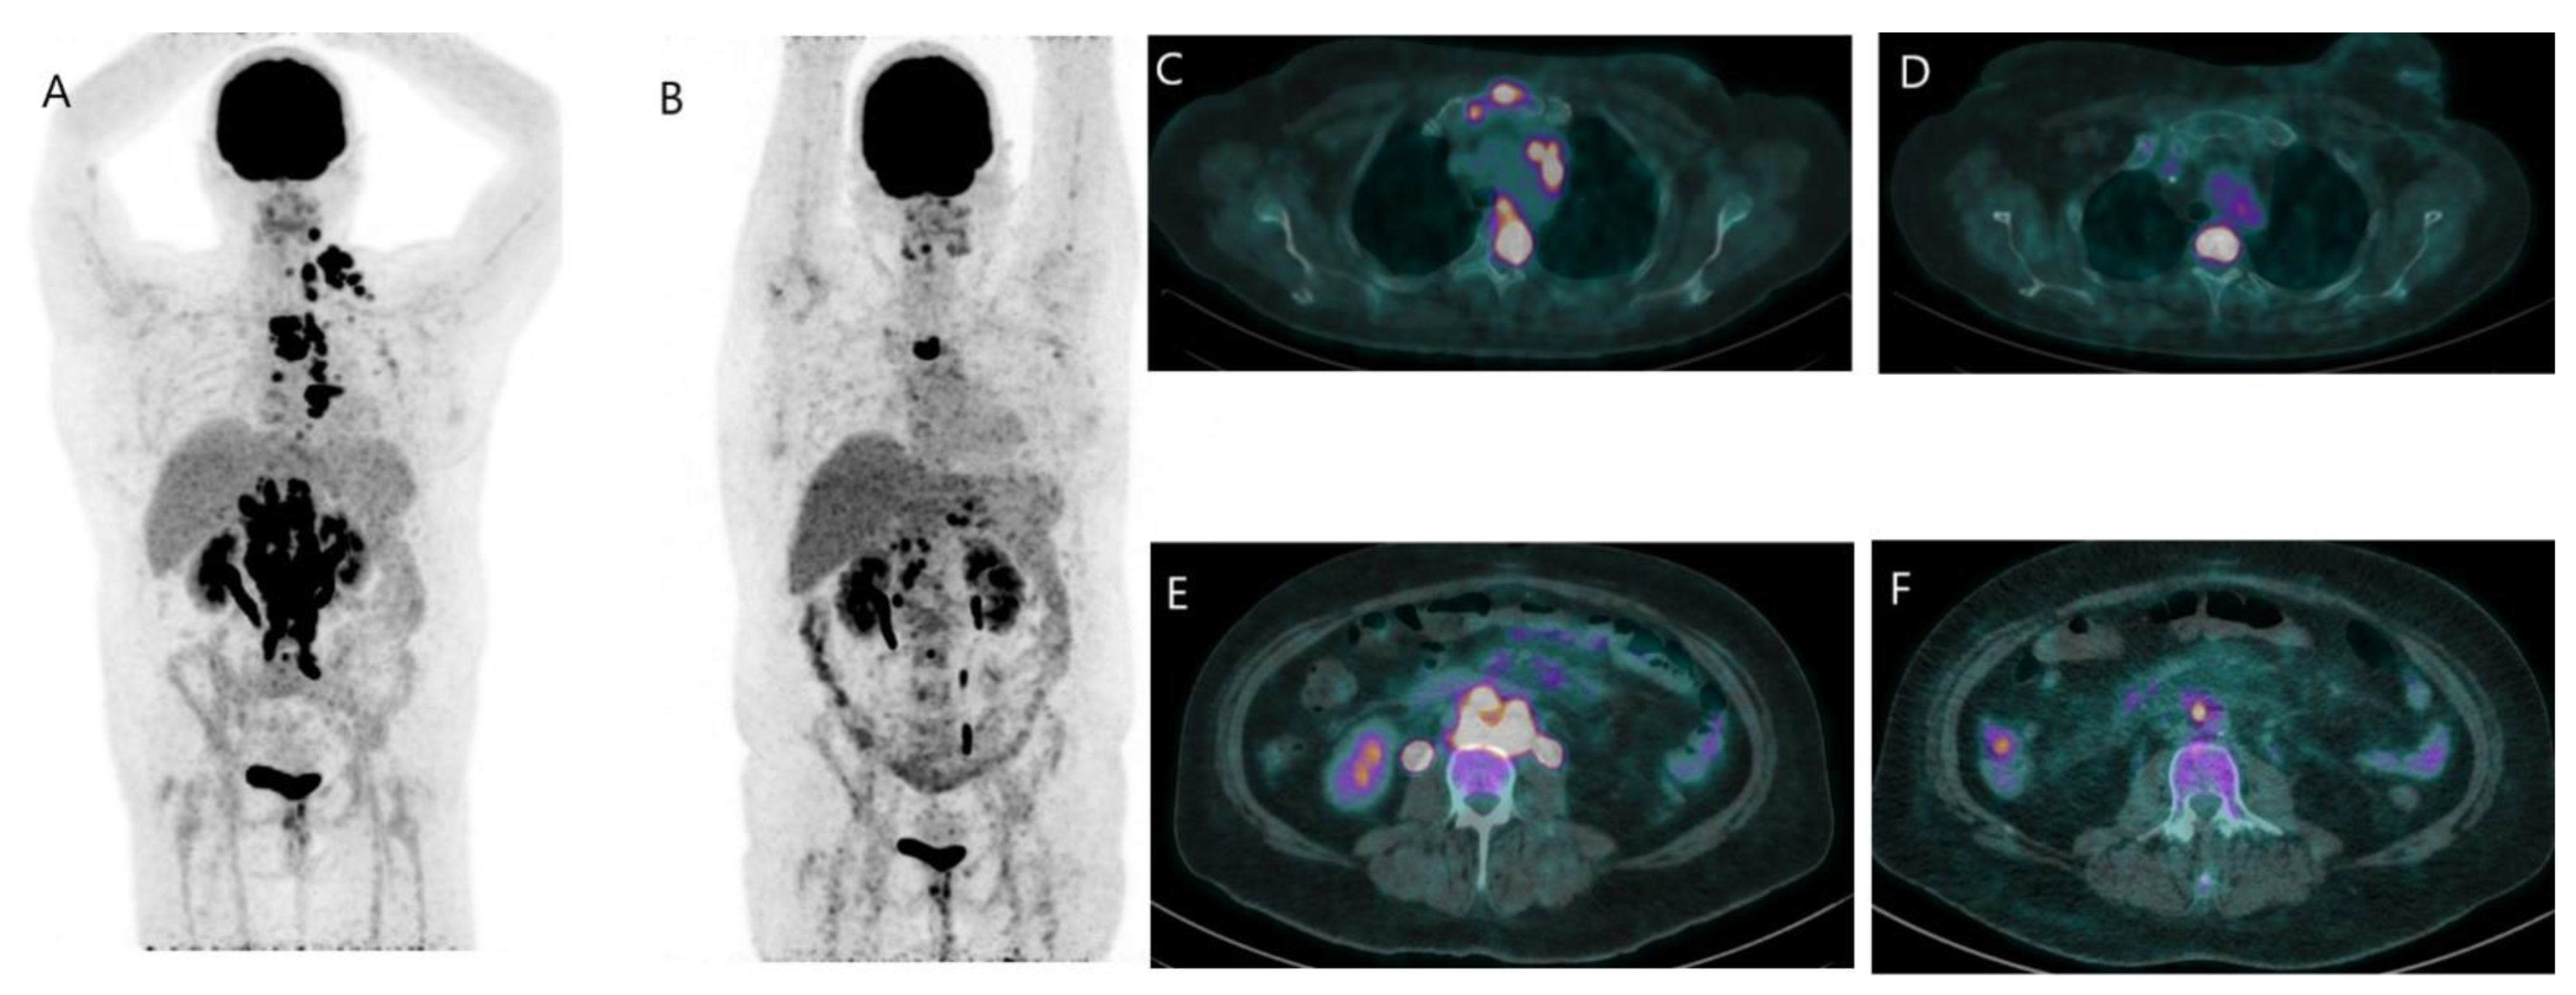

2.3.1. Metastatic Disease

3. FES PET/CT